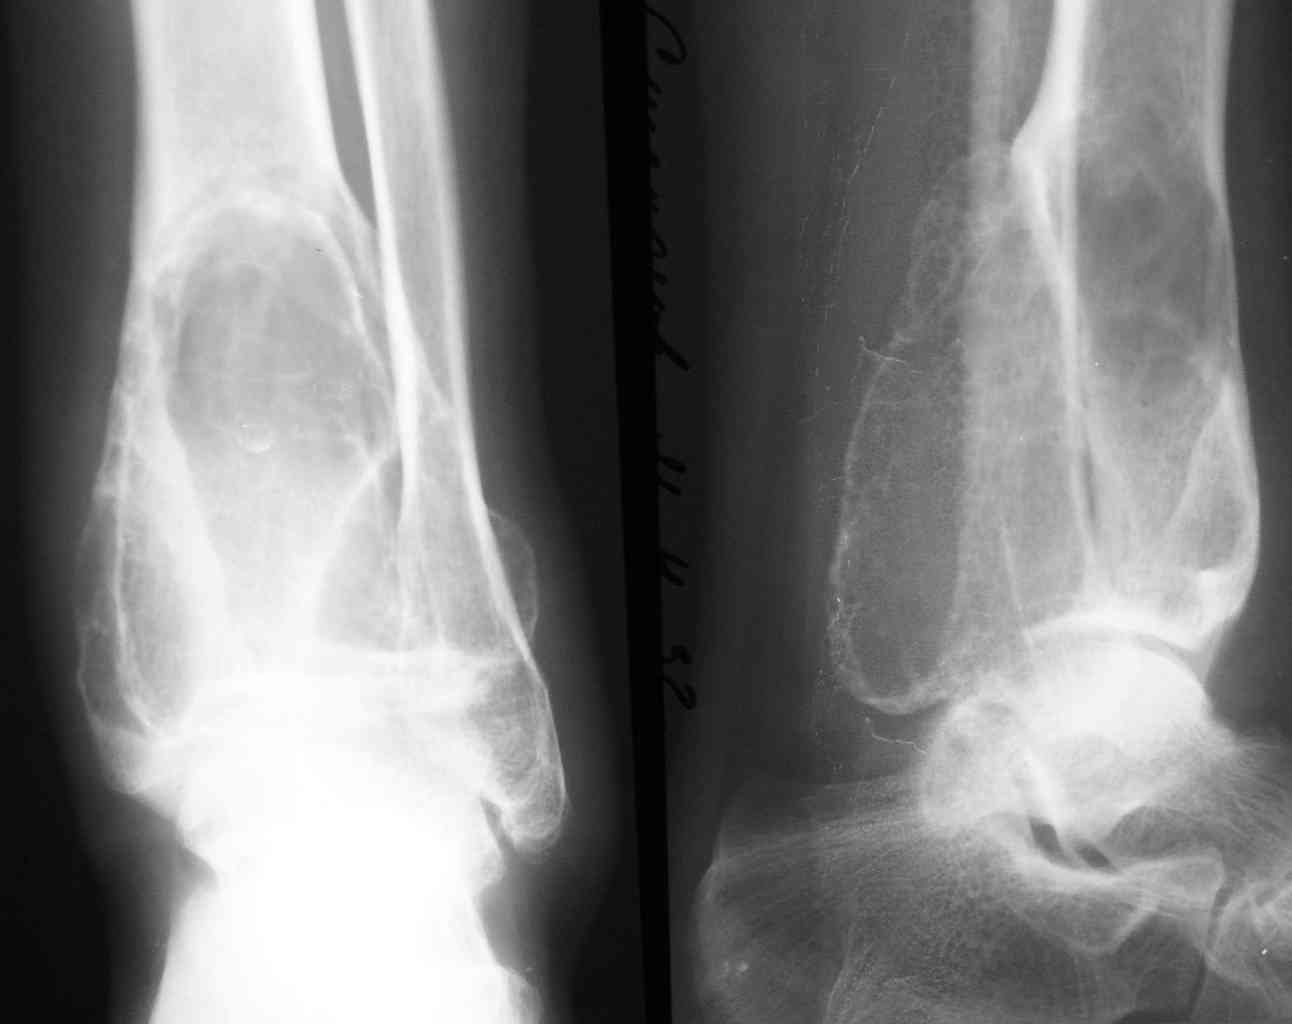

1-Пациент Х.18лет, аневризмальная костная киста малоберцовой кости и основной фаланги I пальца левой стопы (Рис. 1,2).

На представленных снимках рентгенологическая картина АКК не соответствует - в первом случае рентгенологическая картина (учитывая центральное расположение ) более соответствует солитарной костной кисте м.берц. кости, а в фаланге - кистовидная перестройка, во втором случае - гигантоклеточная опухоль